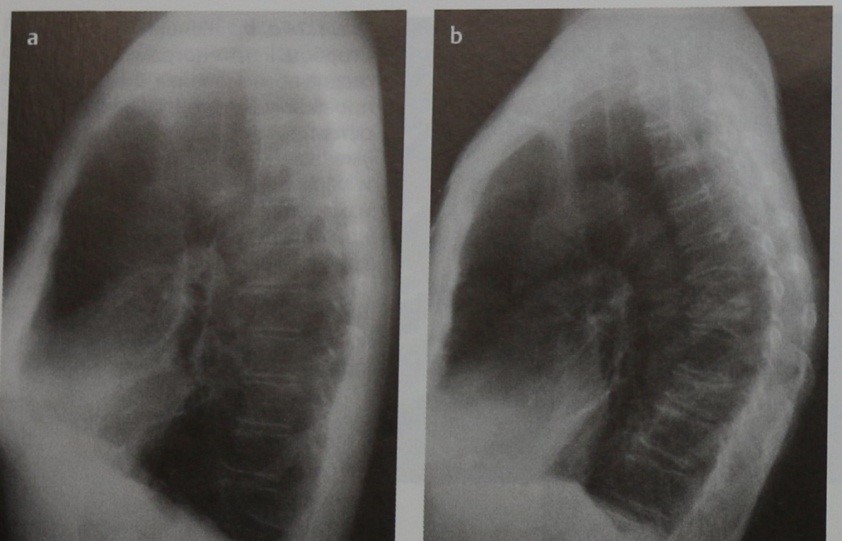

- рентгенография;

На первом рентгенологическом исследовании снимок делают только в положении стоя. В дальнейшем рентгенография проводится в двух проекциях. При функциональном кифозе (сутулости) изменений не фиксируется, так как в момент снимка спина пациента находится в выпрямленном состоянии. Лабораторные анализы в этом случае не требуются. Лечение назначается после осмотра и беседы с пациентом.